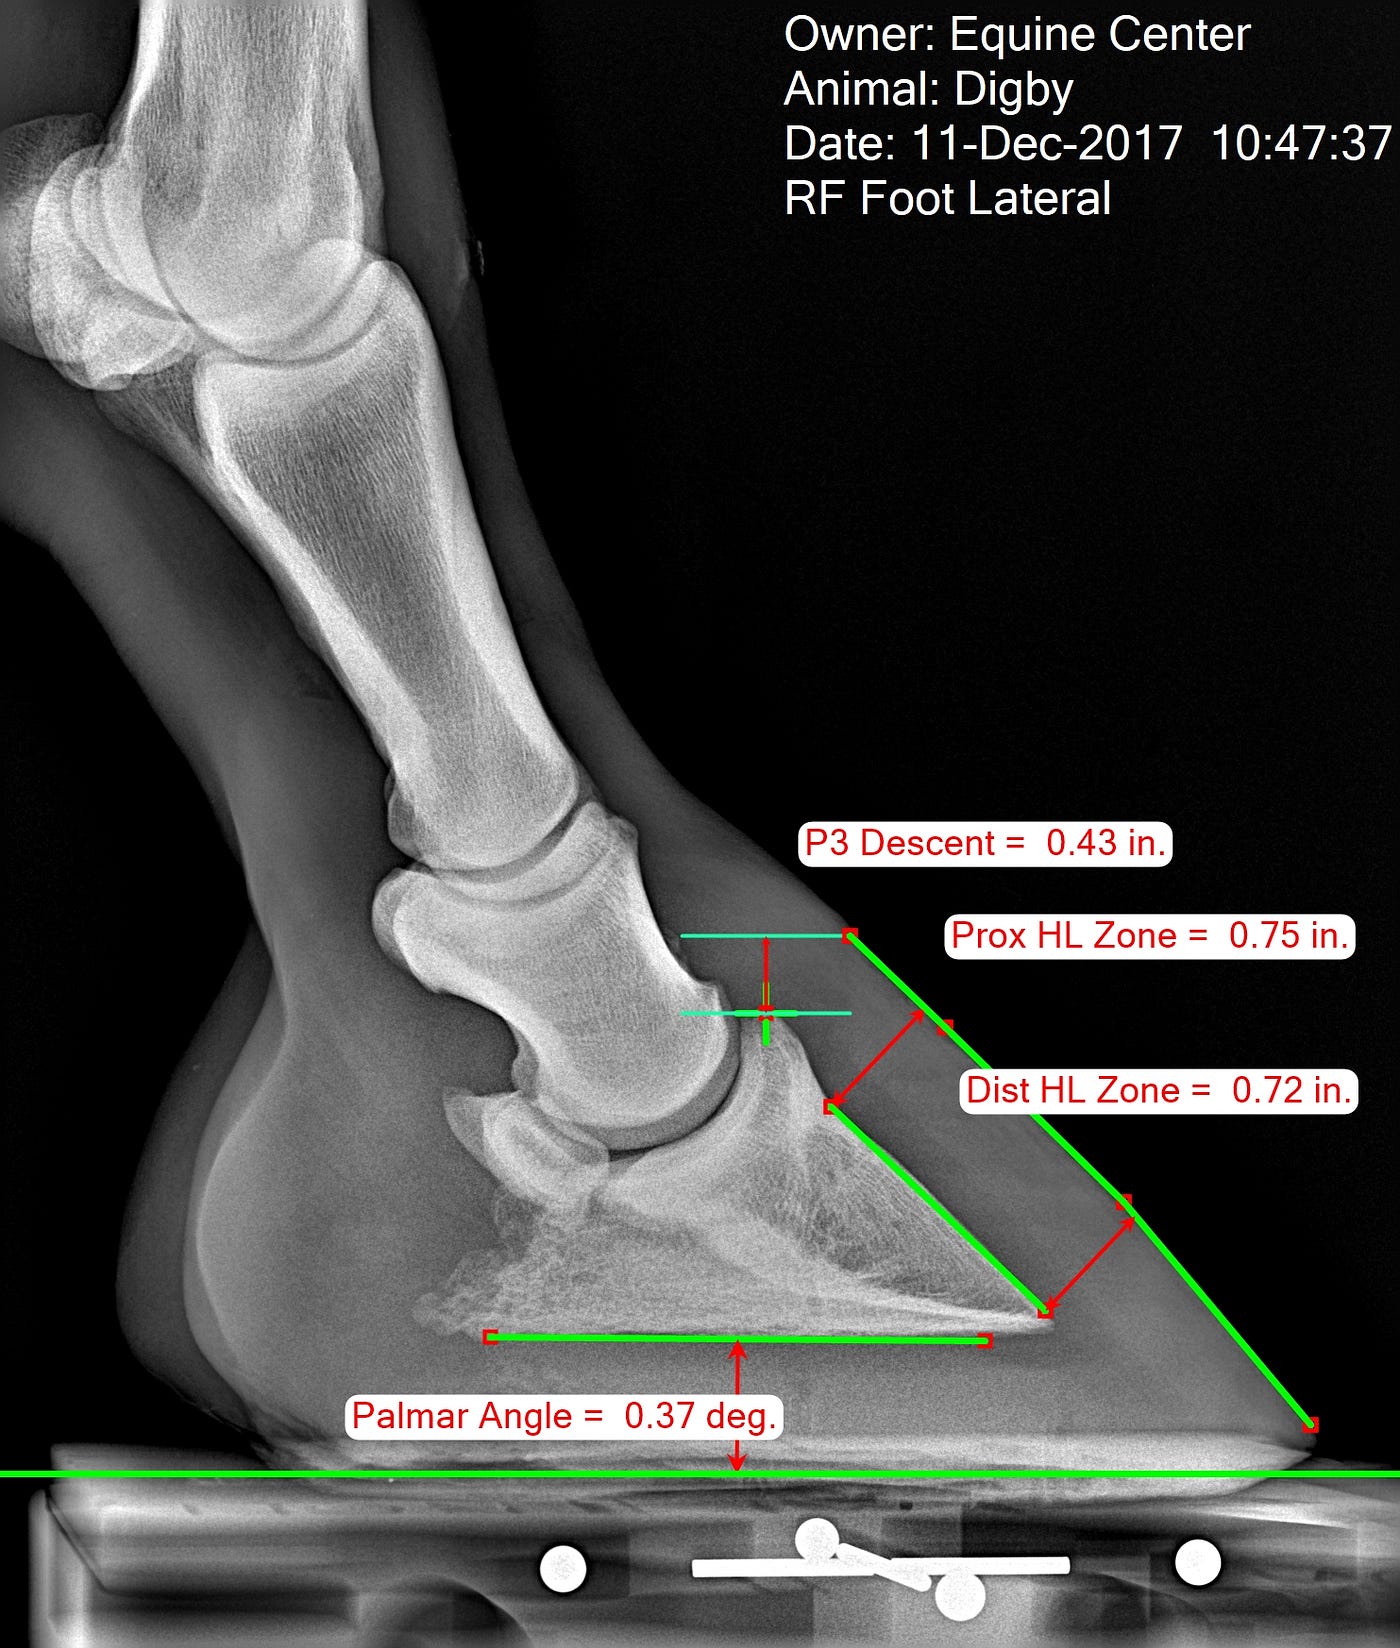

Measuring the Equine Hoof in Radiographs — a Focus on Calibration by

From medium.com

Measuring the Equine Hoof in Radiographs — a Focus on Calibration by How To Measure Hoof Angles The angle of the long pastern bone; The sound the hoof makes; Learning how to measure hooves, and what those measurements mean to the health of your horse, is an important part of natural hoof care. You may have seen your farrier use it. If this angle, or line, is broken, it indicates a poor trim due to either too. How To Measure Hoof Angles.

Measuring the Equine Hoof in Radiographs — a Focus on Calibration How To Measure Hoof Angles This angle is often measured mechanically with the help of hoof gauge. The angle of the long pastern bone; Hoof angle dos and don’ts. Hoof expert susan kauffmann describes three hoof angles you should know to help keep your horse sound. Learn how to identify and assess them. Popular methods to determine the proper hoof angle have relied on: A. How To Measure Hoof Angles.

Measuring the Equine Hoof in Radiographs — a Focus on Calibration by How To Measure Hoof Angles Learn how to identify and assess them. You may have seen your farrier use it. If the horse is working really well, and is comfortable and sound, it might be a good idea to measure the hoof to record the exact angles, lengths, and other measures that make that. The angle of the long pastern bone; Regardless as to whether. How To Measure Hoof Angles.